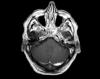

EA: Mujer de 78 años, ingresada por infección respiratoria, acidosis metabólica, hipopotasemia e hipocalcemia moderada. Presenta al ingreso somnolencia y 3 episodios de movimientos clónicos esporádicos de MSI. Se realiza EEG objetivando status focal derecho....

Neurología: Epilepsia | Patología cerebrovascularEtiología: Metabólico | Tóxica-yatrogeniaDiagnóstico final: Status epiléptico focal parieto-temporal derechoNivel de certeza: